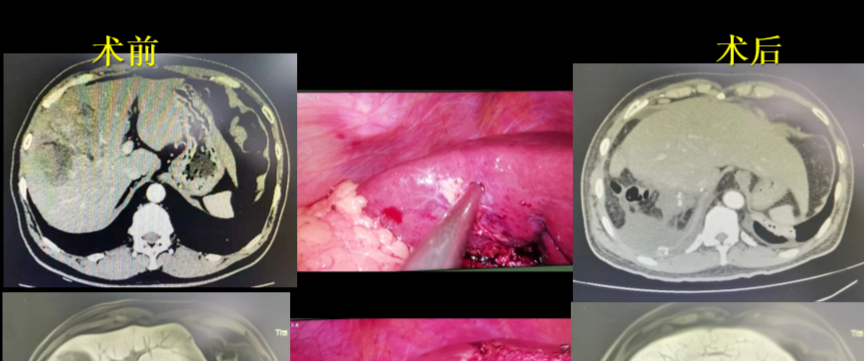

腹腔镜前入路肝切除术治疗右肝巨大肝癌